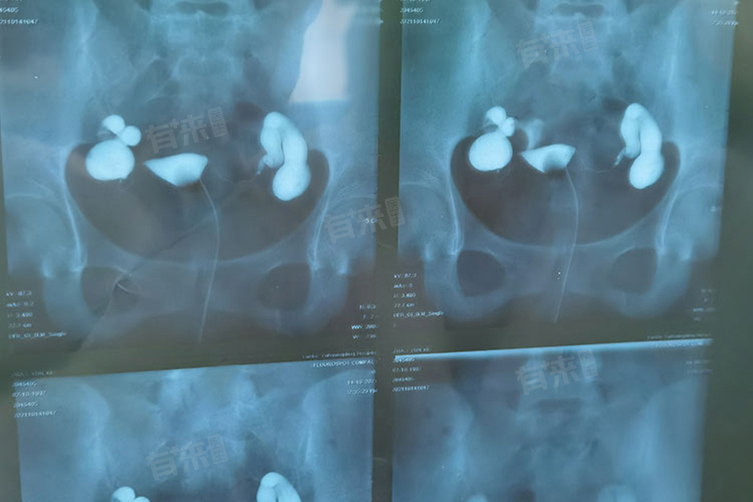

2、输卵管造影术:在X线下,医生通过导管向子宫腔和输卵管内注入造影剂,然后拍摄X光片,造影剂可以清晰地显示子宫和输卵管的形态、轮廓以及输卵管是否通畅。如果输卵管通畅,造影剂会均匀地分布在腹腔内,如果输卵管堵塞,造影剂会在堵塞部位停滞。